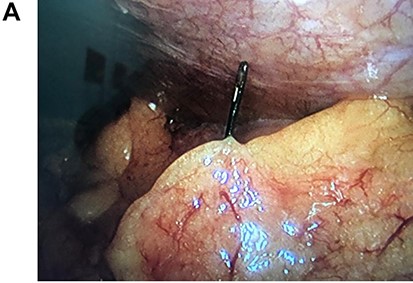

On laparoscopy, multiple adhesions between the omentum and descending colon were seen and released using an ultrasonic energy device (Harmonic, Ethicon US, LLC., Cincinnati, OH, USA). After mobilization of the left colon, the needle was seen stabbing the colonic wall 7 cm away from the splenic flexure. The needle was removed, and the perforation was sutured using a 2-0 absorbable suture without any complications. No other perforations were seen, and the procedure was completed without any complications (Fig. 2A, 2B).